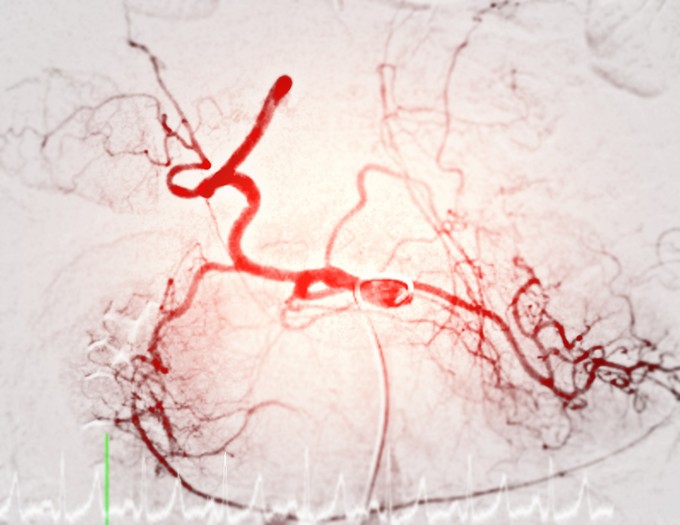

Ezekkel a vizsgálatokkal deríthető ki a szédüléses panaszok oka

Gyakorlatilag majdnem minden szédülést panaszoló páciensnél szükséges bizonyos vizsgálatokat elvégezni.